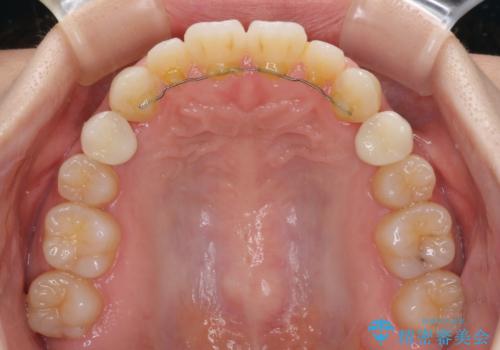

- 歯の欠損による隙間だらけの歯並びを気にして来院された患者様です。

上顎左右1本ずつ欠損していたため、歯列矯正により欠損部位にスペースを集め、その後欠損部位をインプラントにて補綴することとしました。

インビザラインによる矯正治療も提案しましたが、長時間の装着や自己管理が難しいとお考えで、ワイヤーによる矯正治療を行いました。

歯並びは比較的早めに整いましたが、インプラントを埋入するにあたって前後の歯根位置を改善する必要があり、矯正治療に期間を要することとなりました。